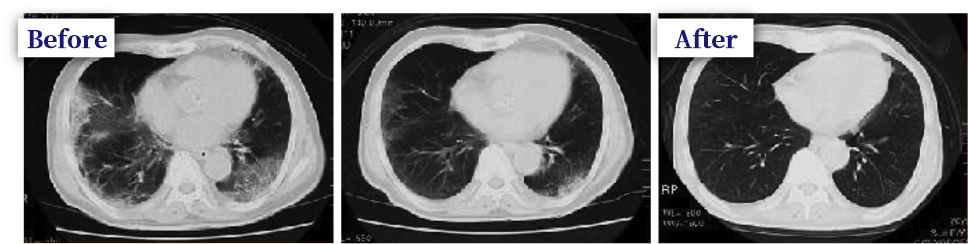

Example of treatment 63 years old male, Mr. D

Mr. C has been smoking for 35 years. A case of obvious pulmonary fibrosis in the chest area.

He was admitted to the hospital as pneumonia without fever. She was treated with antibiotics but did not recover.

After treatment with intravenous gold therapy, the heterotopia almost disappeared and the symptoms disappeared.